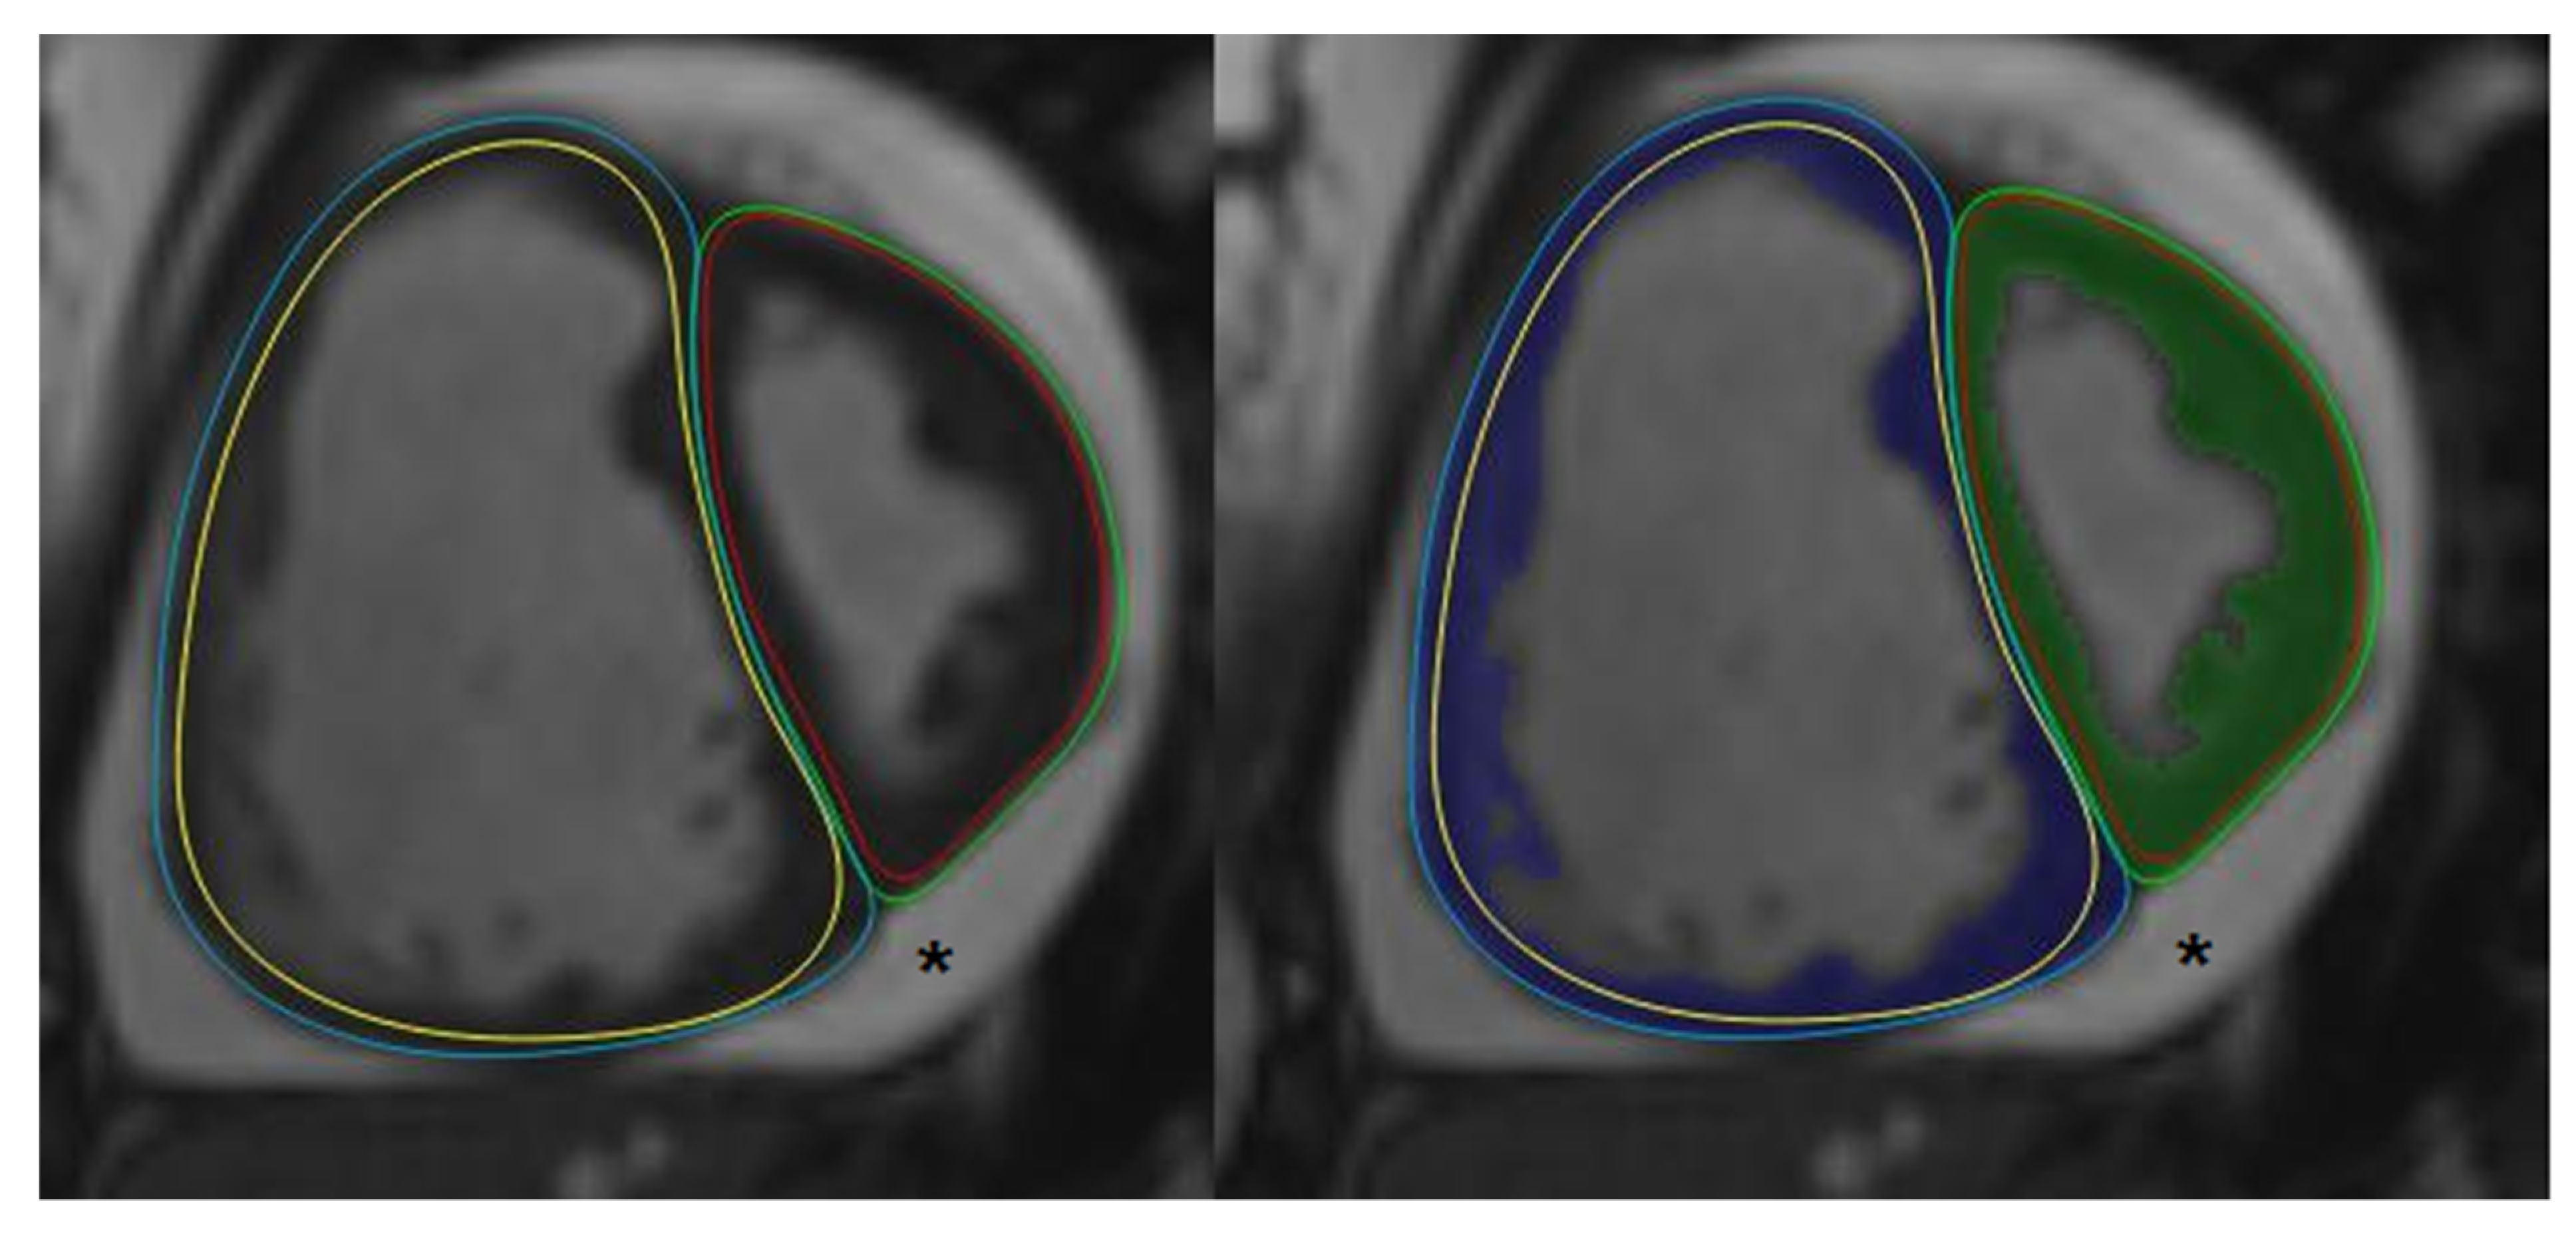

2.2. Cardiac Magnetic Resonance

2.3. Post-Processing